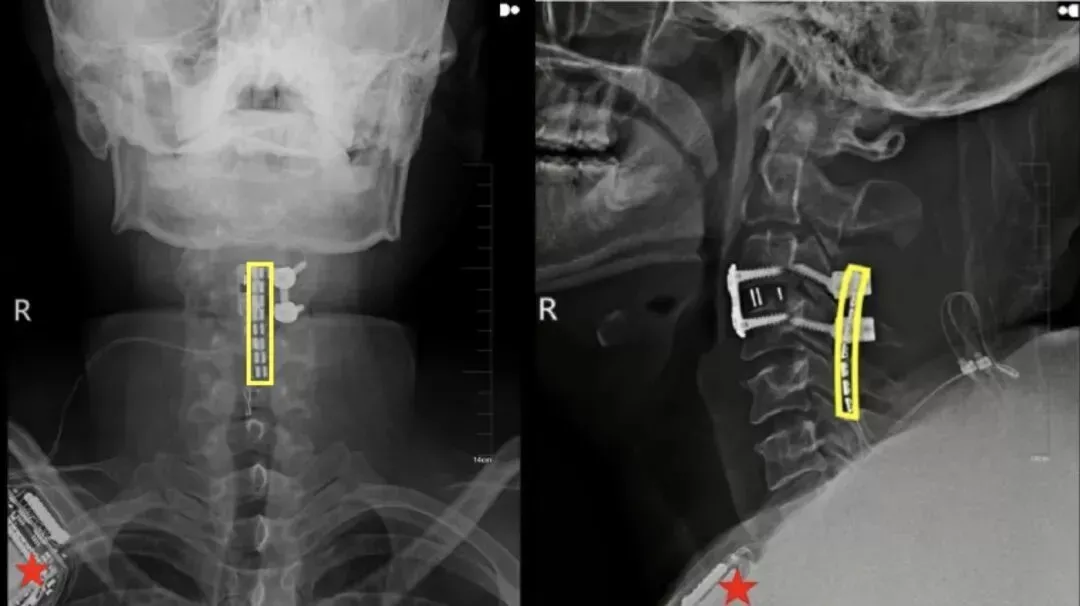

挽救生命是当务之急。刘先生入院后,吉大二院立即启动重伤救治绿色通道,由吴敏飞主刀完成神经减压内固定术。

值得一提的是,手术中,吴敏飞考虑到后续存在着脊髓神经接口植入的可能,同步在颈椎损伤段预留了一个“接口”。